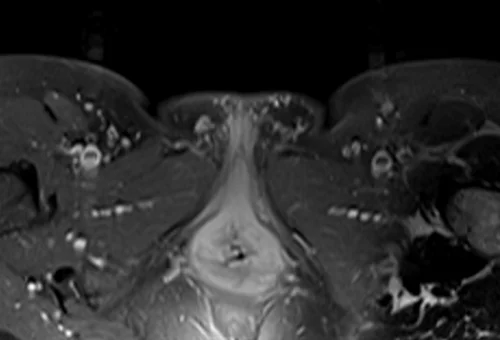

L plexus mri T1 fat saturated post contrast axial images